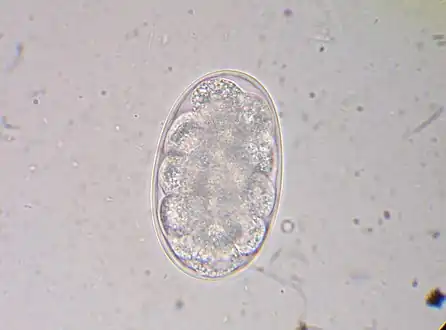

Diagnosis depends on finding characteristic worm eggs on microscopic examination of the stools, although this is not possible in early infection. Early signs of infection in most dogs include limbular limping and anal itching. The eggs are oval or elliptical, measuring 60 by 40 µm, colorless, not bile stained and with a thin transparent hyaline shell membrane. When released by the worm in the intestine, the egg contains an unsegmented ovum. During its passage down the intestine, the ovum develops and thus the eggs passed in feces have a segmented ovum, usually with 4 to 8 blastomeres. As the eggs of both Ancylostoma and Necator (and most other hookworm species) are indistinguishable, to identify the genus, they must be cultured in the lab to allow larvae to hatch out. If the fecal sample is left for a day or more under tropical conditions, the larvae will have hatched out, so eggs might no longer be evident. In such a case, it is essential to distinguish hookworms from Strongyloides larvae, as infection with the latter has more serious implications and requires different management. The larvae of the two hookworm species can also be distinguished microscopically, although this would not be done routinely, but usually for research purposes. Adult worms are rarely seen (except via endoscopy, surgery or autopsy), but if found, would allow definitive identification of the species. Classification can be performed based on the length of the buccal cavity, the space between the oral opening and the esophagus: hookworm rhabditoform larvae have long buccal cavities whereas Strongyloides rhabditoform larvae have short buccal cavities.[19][4][37]

Hookworm egg